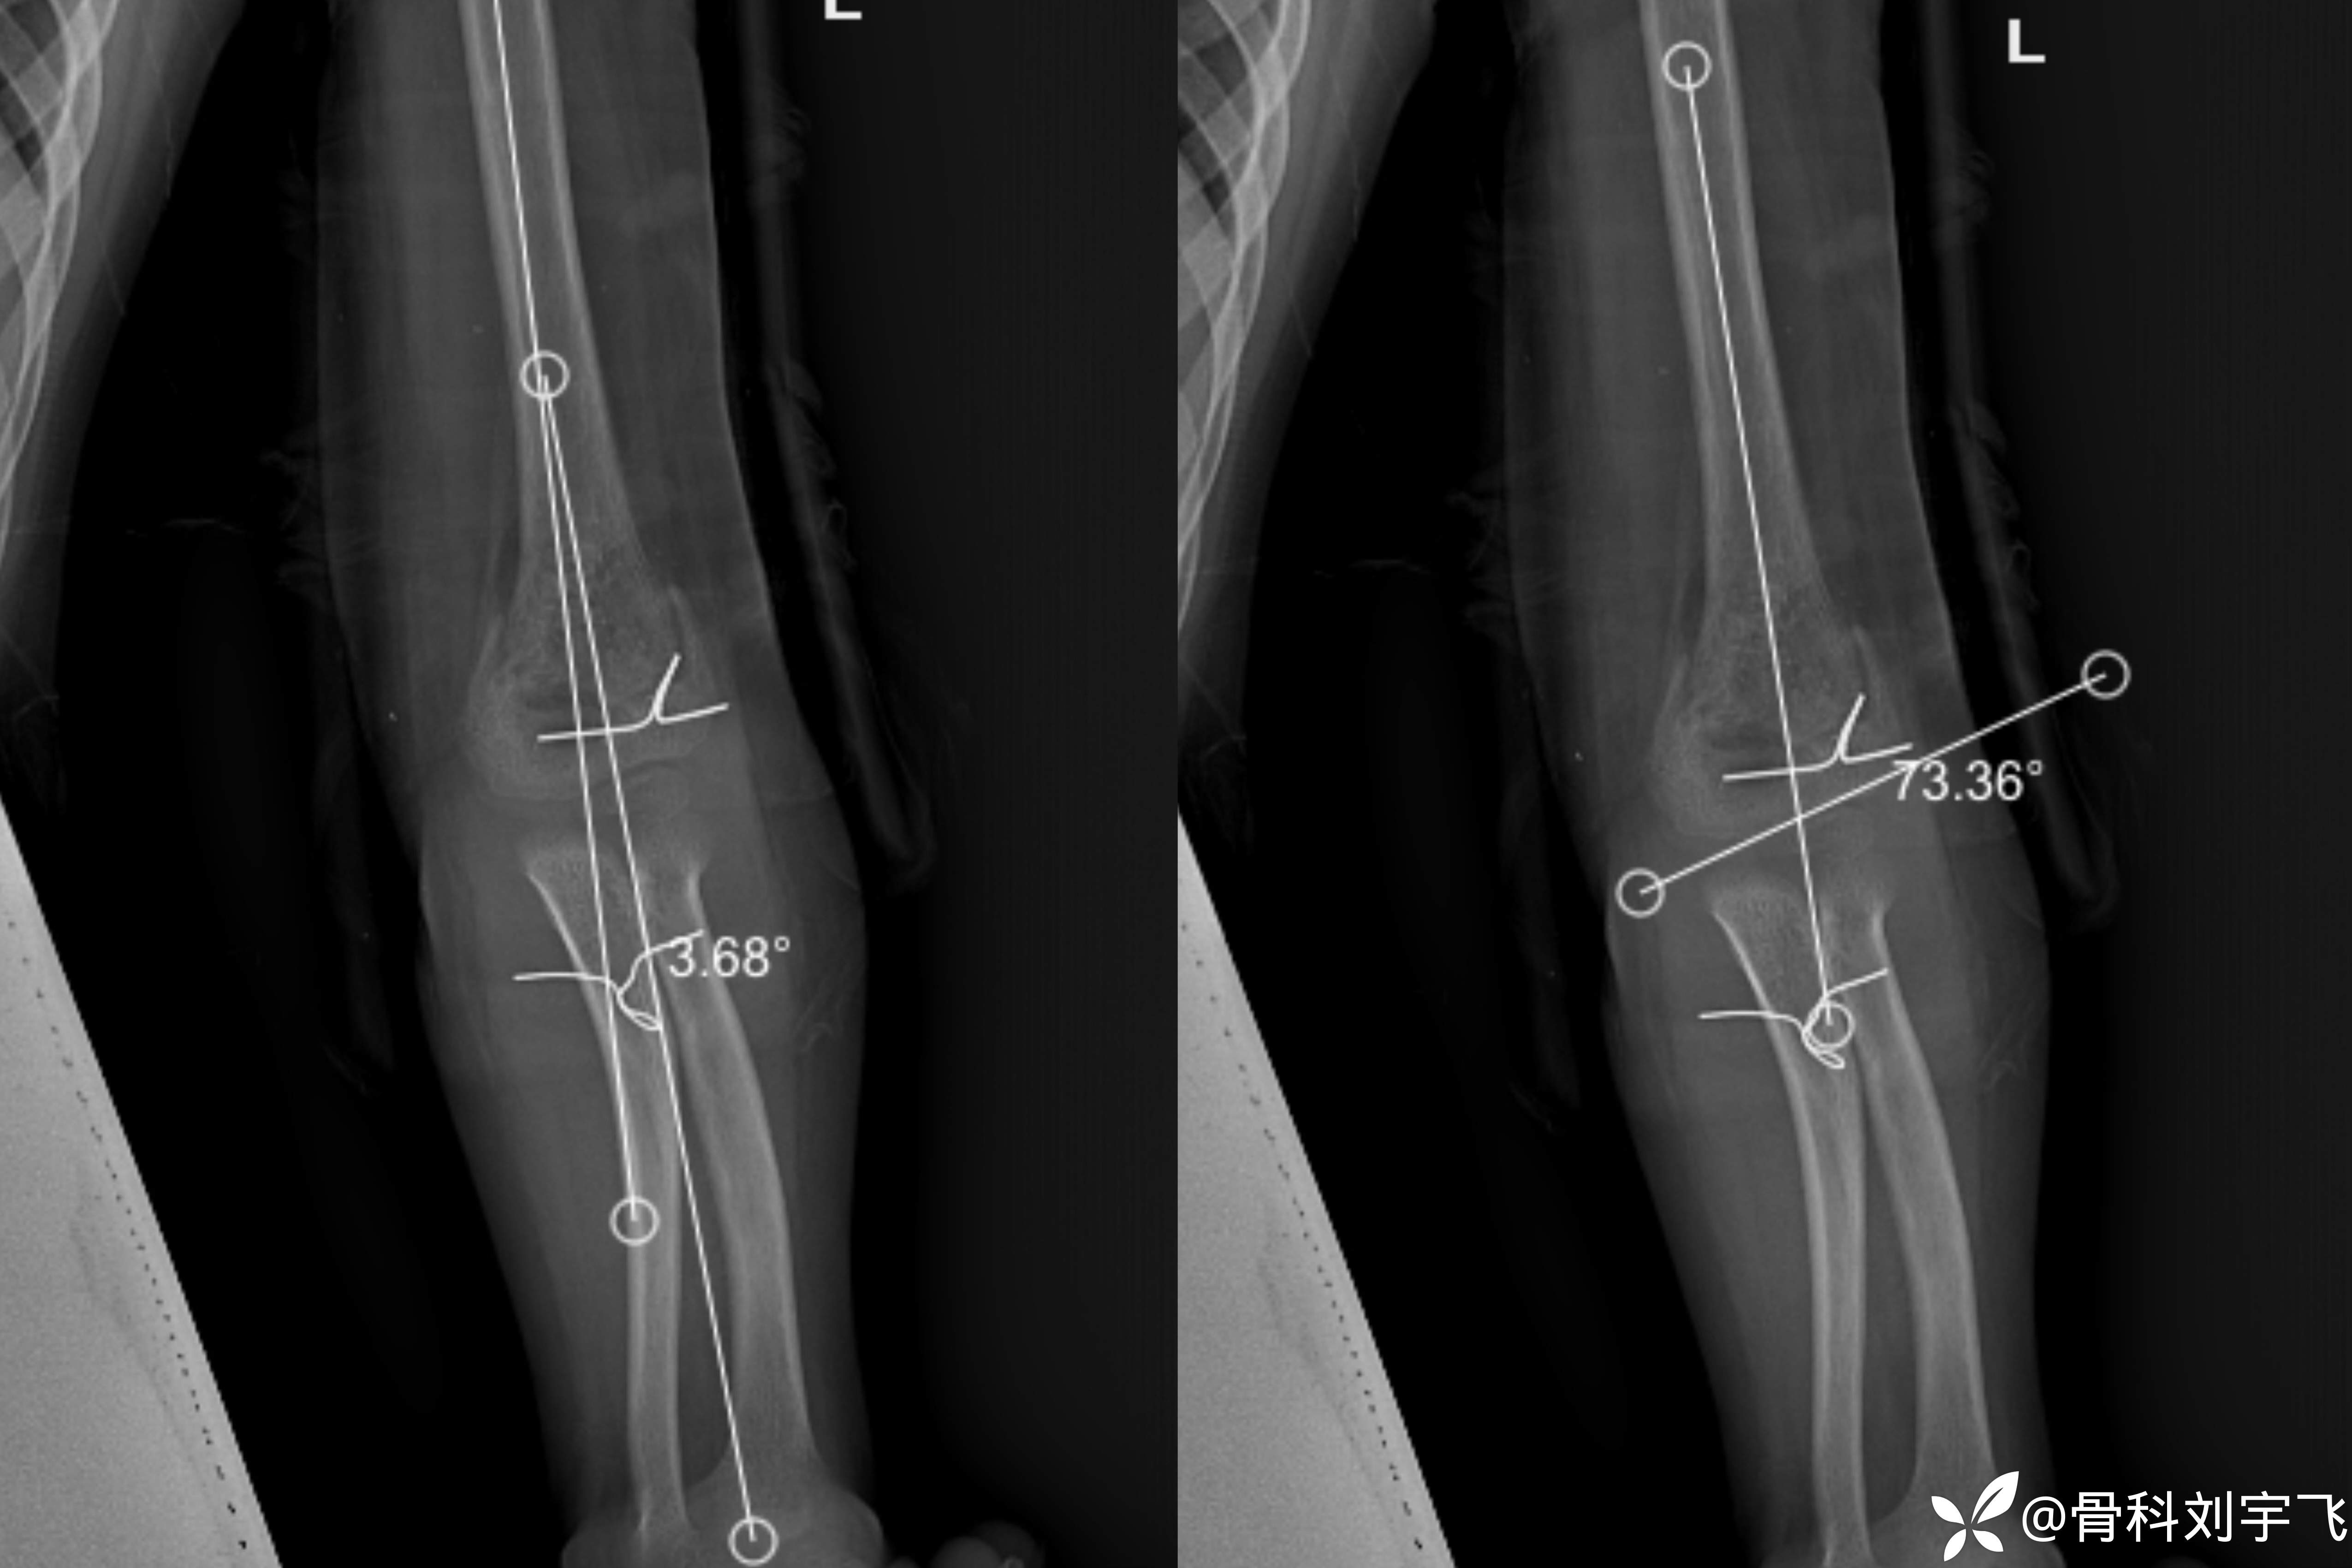

一月时复查:可见骨痂形成测量测量提携角、Baumann角

总结与讨论

提携角 :为肱骨干轴线与前臂轴线相交所成之角,角尖指向上臂,正常值为5°~20°

Baumann角(α)是肱骨长轴和通过肱骨外上髁骺板的直线的夹角。Baumann角的余角(90°- α -5°)即为肘外翻角

Baumann角的正常值范围为75°~80°,Williamson等扩展到64°~81°。

测量Baumann角有助于评价儿童肱骨髁上骨折复位效果。